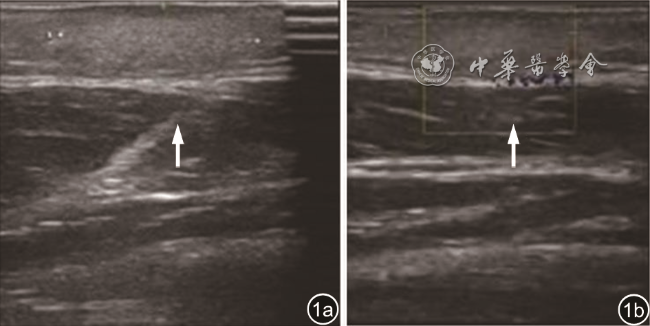

图2 左大腿包块CT增强图像示皮下脂肪内斑片状密度增高影,未见明显强化(箭头所示)。图a为横断位图像;图b为矢状位图像